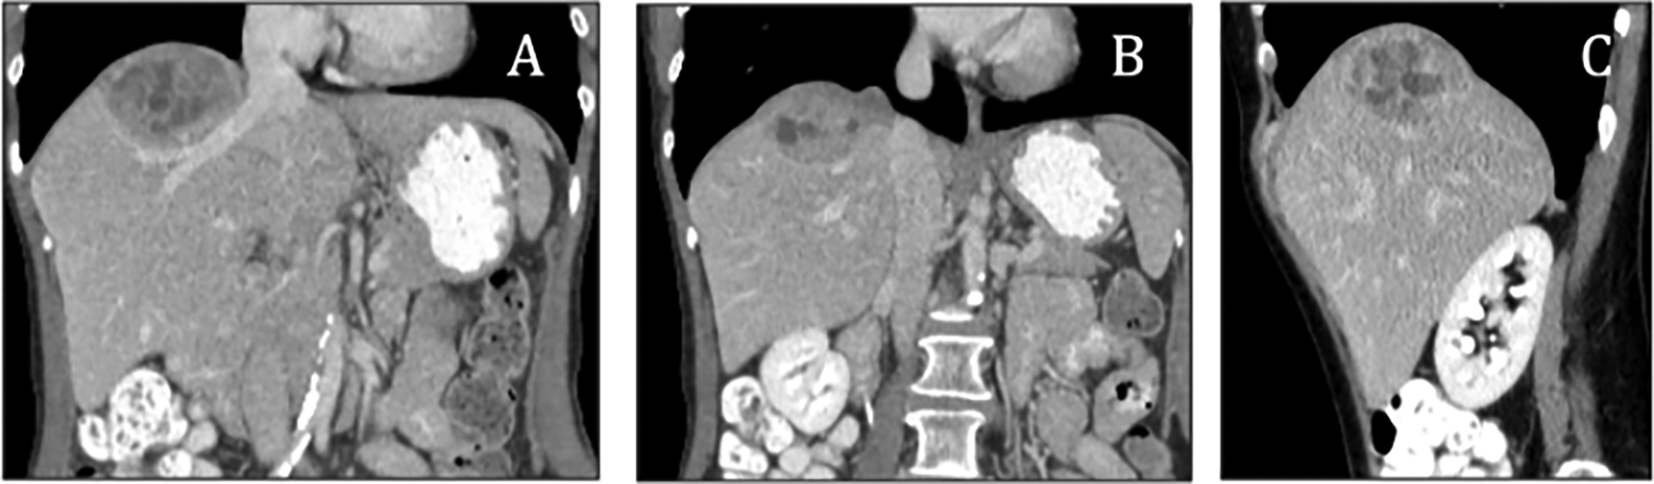

A computed tomography (CT) scan of the abdomen revealed a large, heterogeneous solid mass in the right lobe of the liver (Figure 1). Subsequent PET/CT imaging indicated mild activity in the hepatic mass (Figure 2). Laboratory evaluations demonstrated markedly elevated levels of urinary metanephrines, with total metanephrines measured at 10,211 mcg/24 hours (urinary metanephrines at 3,375 mcg/24 hours and urinary normetanephrine at 6,836 mcg/24 hours). Additionally, her blood norepinephrine level was found to be 702 pg/ml. During the surgery, a diaphragmatic paraganglioma was discovered and subsequently resected (Figure 3).